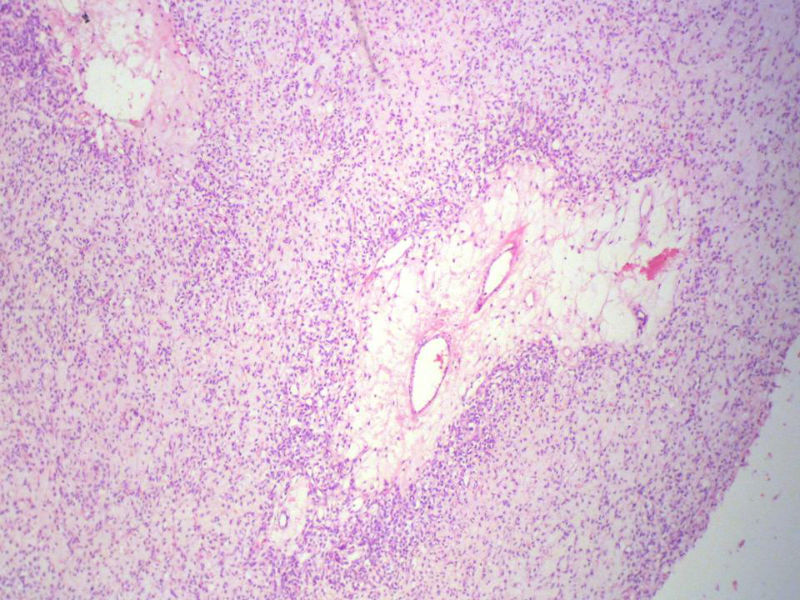

男,27岁,右股骨上段皮下肿物1年余,无明显疼痛,检查肿物明显隆起于皮下,边界清楚,手术完整切除肿物。肉眼,肿物6X6X5厘米,外观多结节状,似有包膜,切面灰白色,质韧。

特别提示:镜下核分裂3-4/HP.

3. 本例组织学改变与粘液性脂肪肉瘤,粘液样纤维肉瘤,纤维粘液样肉瘤,骨外粘液样软骨肉瘤都有重叠之处,且镜下并未见典型结构。由此,免疫组化结果就尤显重要。特别是专业书籍提到,突触素或嗜铬素阳性,对鉴别诊断有重要意义。我用CGA,也是在以上几个肿瘤中举棋不定而为。NSE和CK没用,其实我想用更多的抗体来证实更多的东西,但患者的经济条件不太好,遗憾!